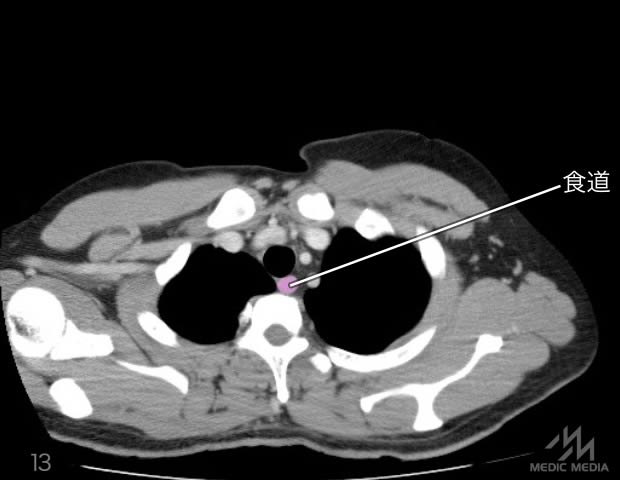

造影CT

スライド(画像下)を動かしながら,CTで臓器の位置を確認してみましょう.

消化器